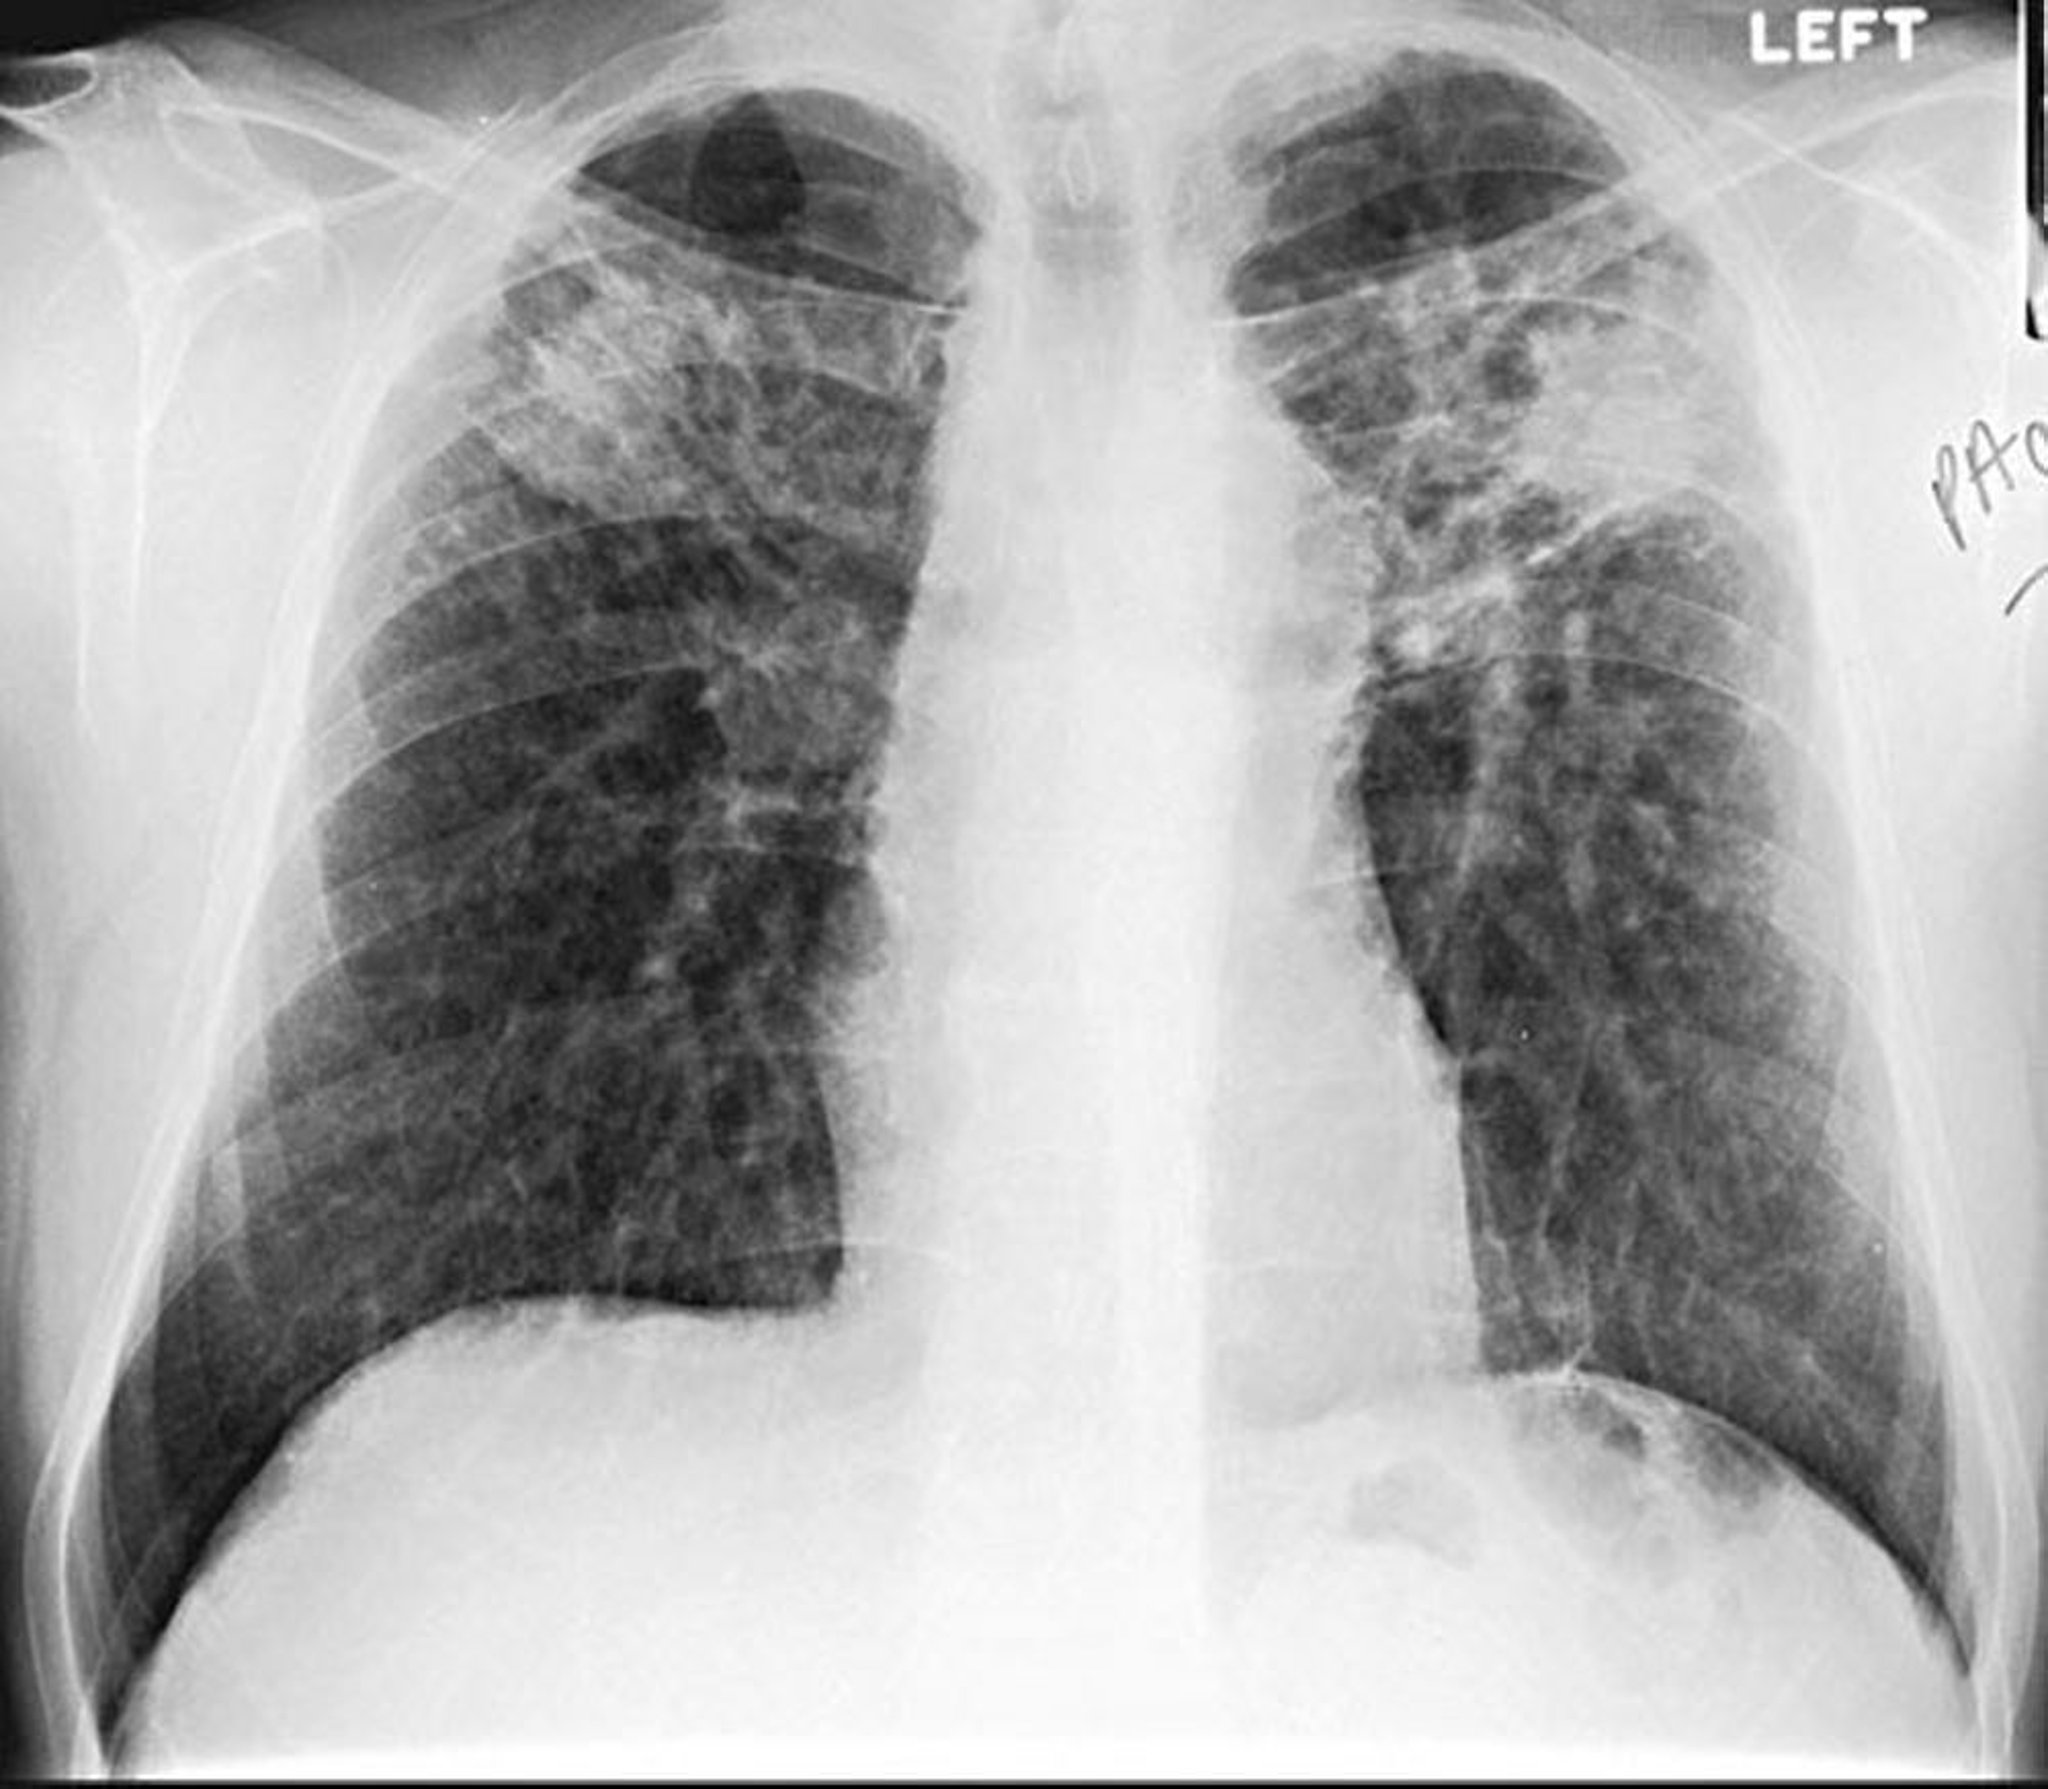

Силикоз-конгломерат

Image courtesy of David W. Cugell, MD.

Силикоз